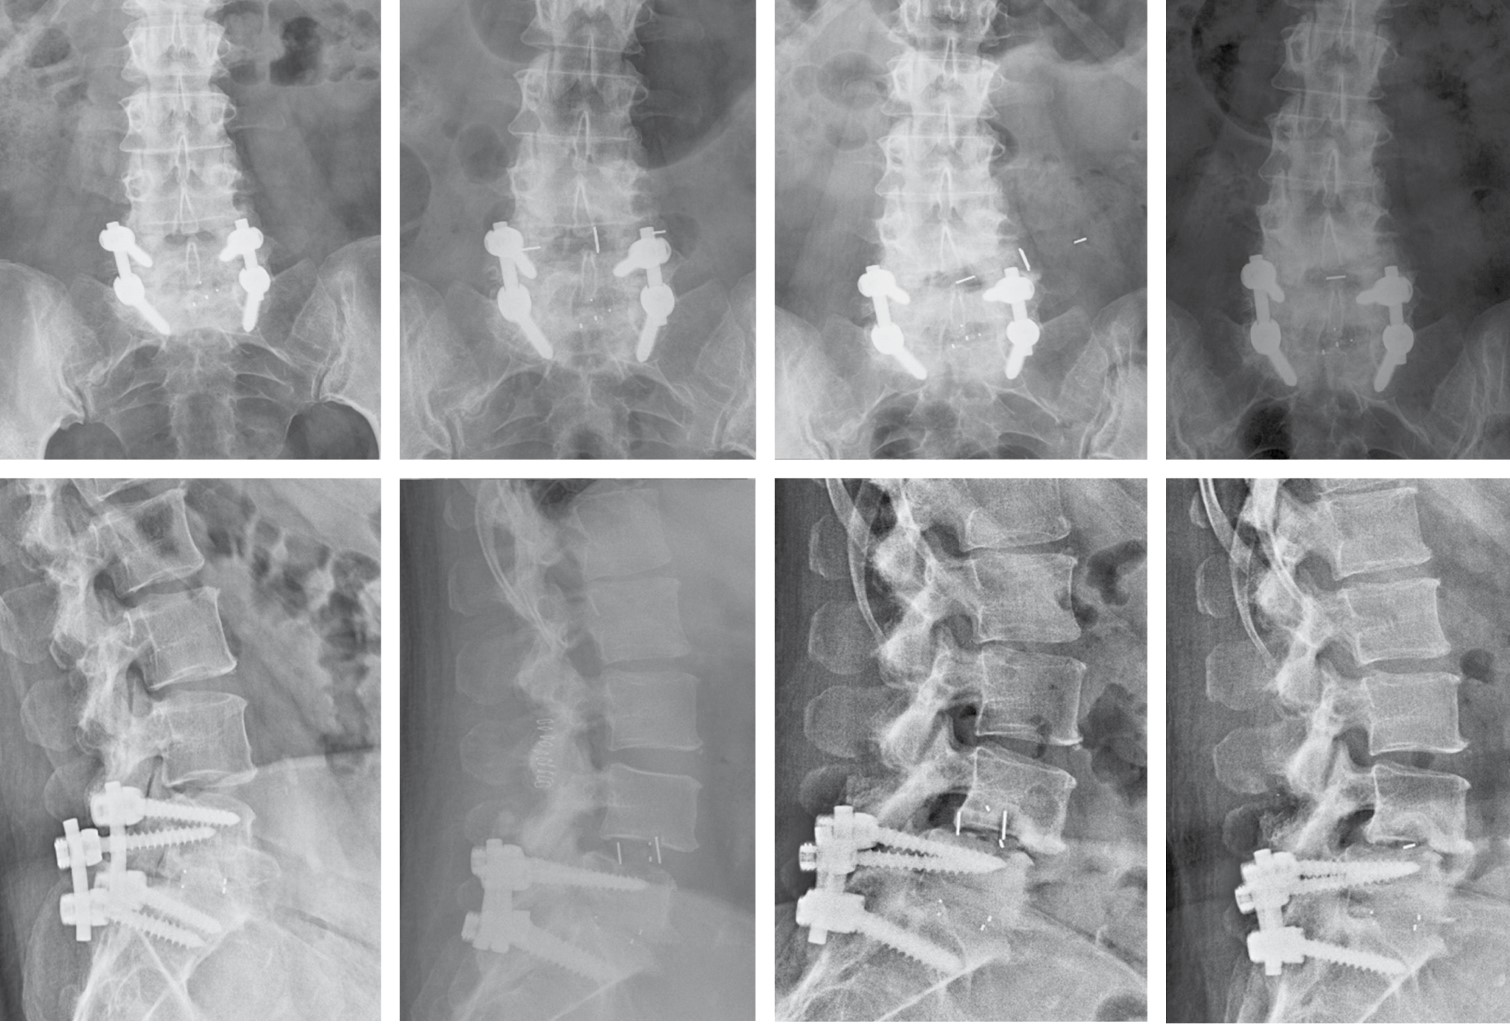

Como complicaciones tardías locales mayores, cabe señalar que no se encontró ningún caso de fístula de líquido cefalorraquídeo o seudomeningocele, ninguna fibrosis perirradicular, hernia abdominal ni infección. Pero se recogieron dos casos de fractura vertebral, una recidiva clínica y una movilización de caja, sin encontrarse diferencias estadísticas entre los grupos. Fractura L4: paciente varón de 85 años con artrodesis lumbar L4-L5 TLIF, hace años que fue intervenido en Noviembre de 2016 realizándose LLIF L3-L4 (PEEK), presenta fractura de L4 en Enero de 2017 (dos meses postquirúgicos) realizándose mediante abordaje bilateral de Wistle retirada de material TLIF previo y artrodesis con tornillos pediculares L2 a L5 (Figura 4). Fractura L3: Paciente mujer 67 años con artrodesis lumbosacra L4-S1 previa que fue intervenida en julio de 2017 realizándose LLIF L3-L4 (titanio), presenta fractura de L3 en Marzo de 2018 que fue intervenida realizándose en un primer tiempo lateral colocación de caja de corrección hiperlordótica. En un segundo tiempo mediante abordaje posterior, extracción de tornillos y barras y se amplía la artrodesis posterior D11-S1 (Figura 5). Movilización caja: mujer de 48 años con antecedentes de artrodesis L5-S1 se intervino en Julio de 2017 realizándose LLIF L4-L5 (PEEK) mediante técnica stand-alone, a las cinco semanas de la cirugía comenzó con un importante dolor lumbar irradiado a miembro inferior izquierdo. El estudio de imagen demostró una movilización mayor de 10 mm. Como tratamiento quirúrgico se procedió a la retirada de la caja por la misma vía transpsoas y ante la imposibilidad de colocar nuevo implante debido a la rotura parcial de la caja y al alto riesgo de lesionar el nervio femoral se decidió rellenar el espacio intersomático mediante injerto con DBM (Figura 6). Recidiva: paciente varón de 82 años con artrodesis lumbar L4-L5 PLIF, hace años que fue intervenido en Julio de 2017 realizándose LLIF L3-L4 (PEEK), presenta recidiva clínica (dolor lumbar y radicular) en Diciembre de 2017 (cinco meses postquirúrgicos), se realizó mediante abordaje posterior descompresión mediante laminectomía L3. Cuatro pacientes (13.8%) fueron reintervenidos (con retirada del implante (movilización y una fractura) y se añadió cirugía de fijación posterior (con descompresión en el caso de la recidiva). El estudio comparativo de las complicaciones no evidenció diferencias respecto al tipo de caja (p = 0.33) ni con respecto a la necesidad de reintervención (p = 0.624) ni a la de retirada de la caja (p = 0.523) (Tabla 5).

Figura 5